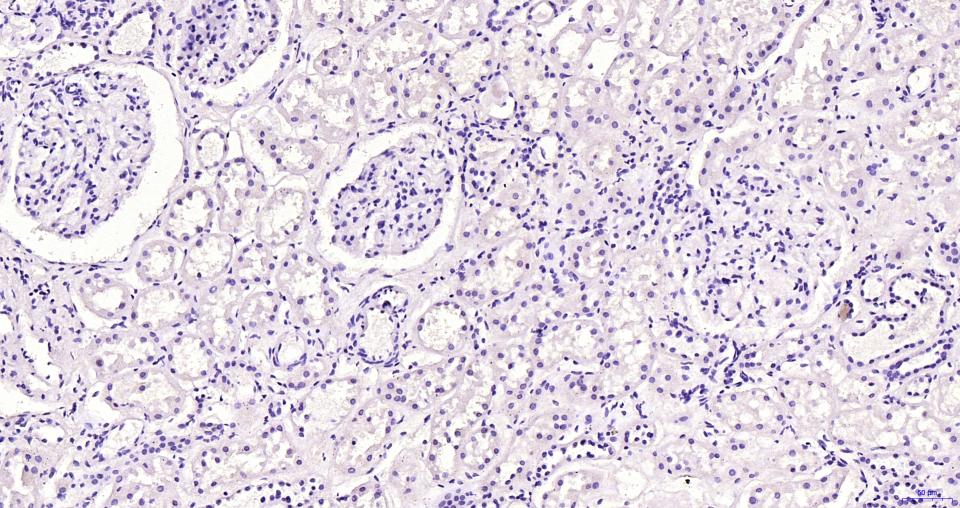

(Negative control) Paraformaldehyde-fixed, paraffin embedded Human kidney; Antigen retrieval by boiling in sodium citrate buffer (pH6.0) for 15 min; Antibody incubation with Human CG beta Monoclonal Antibody, Unconjugated(bsm-43172M) at 1:200 overnight at 4°C, followed by conjugation to the bs-40296G-HRP and DAB (C-0010) staining